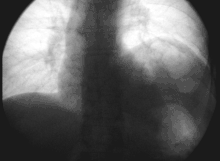

أثناء جراحة الصدر يجب التعرف على العصب الحجابي والحفاظ عليه. أثناء عملية زراعة الكبد من الممكن جرح العصب الحجابي بواسطة ملقاط الوريد الأجوف السفلي.[3] قطع العصب الحجابي أو استئصال الحجاب،[4] يؤدي إلى شلل نصف الحجاب الحاجز. تخطيط الموجات الصوتية هو أفضل طريقة لإظهار شلل الحاجز. سيكون من الصعب التنفس ولكنه سيستمر طالما النصف الأخر ما زال سليماً.

مقطع عرضي في الصدر،, showing relations of pulmonary artery.